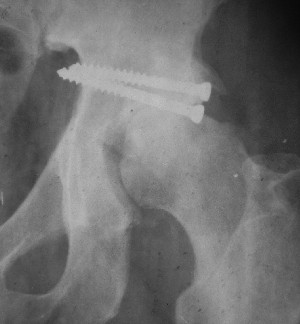

При поступлении в госпиталь 3.06.03

Больной 18 мая 2003 года в автоаварии получил перелом левой вертлужной впадины, вывих бедра. Госпитализирован в один из стационаров области.Вывих вправлен. В последствии бедро вывихивалось еще дважды. На консультацию был представлен снимок от 19.05.03г., больной переведен к нам 3.06.03г. Снимок при поступлении - перелом впадины, задне-верхний вывих бедра. 05.06.2003 г. выполнено открытое вправление вывиха левого бедра и остеосинтез стенки вертлужной впадины двумя винтами. Послеоперационный период без осложнений. Объем движений в левом тазобедренном суставе восстановился полностью. Выписан на амбулаторное лечение в удовлетворительном состоянии с рекомендациями 3 месяца ходить на костылях без нагрузки на оперированную конечность. На контрольных рентгенограммах левого тазобедренного сустава 13.10.2003 г. - признаки консолидации перелома; плотность, форма головки и состояние суставных поверхностей удовлетворительные. Разрешена дозированная осевая нагрузка, на конечность с использованием дополнительной опоры. 19.12.2003 г. больной обратился с жалобами на боли в левом тазобедренном суставе. На рентгенограммах левого тазобедренного сустава 19.12.2003 г., 20.02.04г. - асептичекий некроз головки бедра. 5.04.04г. - эндопротез. Сейчас ходит без трости, не хромает. Особенность эндопротезирования - при удалении винтов прослежена линия перелома заднего края впадины и предложено установить чашку несколько меньшего диаметра, чтобы она была покрыта несломанной частью.